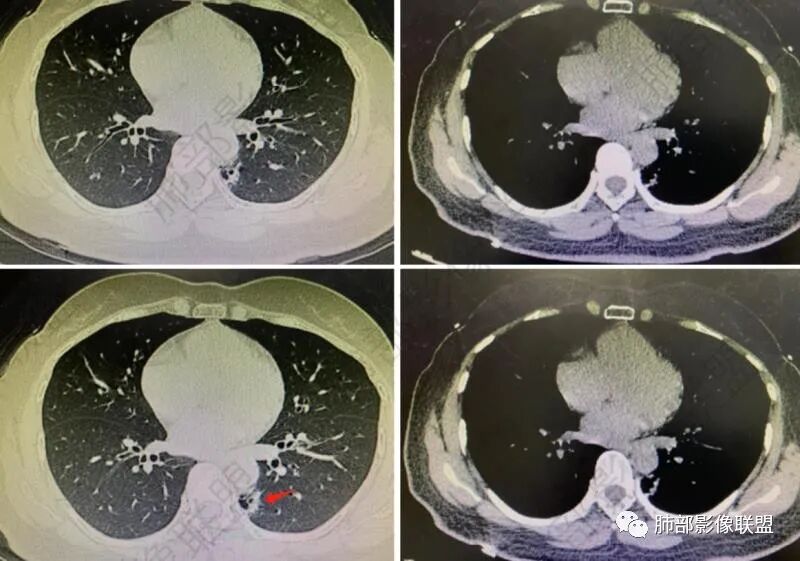

左肺下叶胸膜下不规则结节,边界清,短毛刺及囊腔,假大空 支气管扩张,邻近胸膜增厚,右肺上叶磨玻璃结节,边界清,考虑左肺下叶腺癌,右肺上叶AIS,鉴别炎性结节、隐球菌。

左肺下叶后基底段结节,边缘凸起,不规则,血管进入,假太空及小叶间隔特点(恶性征象之一),另结节壁层胸膜下脂肪间隙消失,两肺多发散在磨玻璃结节,右肺上叶后段圆圈征,双肺下叶胸膜下分布,纵隔内淋巴结肿大,考虑粘液腺Ca并两肺气道种植转移,与PC鉴别,建议隐球荚膜抗原检查。

右肺上叶磨玻璃结节,边缘清晰,考虑AAH。左肺下叶脊柱旁结节,周围见多发空泡,边缘模糊,胸膜粘连,考虑肉芽肿可能。

综合分析考虑恶性原发性囊腔型肺腺癌肺转移或者肠道、生殖系统、泌尿系统肿瘤肺转移。

左肺下叶胸膜下病灶,考虑炎性肌纤维母细胞瘤,鉴别肺梗,右肺上叶磨玻璃结节,不典型腺瘤样增生。

右肺上叶亚实性结节考虑炎性病变,左肺下叶胸膜下结节,边缘不光整,局部胸膜增厚,考虑瘾球菌感染,腺癌不排除。

左肺下叶靠近胸膜囊腔样结节,右肺上叶纯磨玻璃结节,青年女性,查体发现,无症状,考虑腺癌可能性大。

右上肺磨玻璃结节,AIS、左肺下叶结节,边界不规则,考虑肉芽肿性病变,隐球?

右肺上叶磨玻璃结节,考虑原位癌可能性大,左肺下叶实性病灶,形态不规则,空泡,考虑浸润性腺癌。

右肺上叶原位腺癌/微浸润腺癌,左肺下叶高密度影,边缘磨玻璃影,内见空洞,浸润性腺癌。

右肺上叶纯磨玻璃结节,界清,考虑aah或AIS。左肺下叶结块,界清不规整,内见空洞与支气管通,支气管壁增厚不明显,考虑肺隔离症,结核,腺癌不除外,建议CTA检查,视频两下肺多发磨玻璃结节,考虑炎性改变。

囊实性?这部位,第一印象要警惕--隔离症

隔离症——需要增强确定,看起来附近似有体动脉正常,没增强底气不足。

真菌?不太符合,因为囊腔。如果不考虑隔离症?就要警惕腺癌系列,总体看来不是很支持。

1、右肺上叶混合密度磨玻璃结节特征性较强,尤其是后段病灶,边界清楚,应高度警惕微浸润腺癌,这个不用纠结,我们可以等,定期复查行之有效。

左肺下叶背段脊柱旁病灶相当不规则,形态既不符合空洞,也未能围成一完整的囊圈影,未见典型的分叶、毛刺及清楚的磨玻璃晕,前方出入支气管轻度扩张,纵隔窗病灶密度偏高不均,临近胸壁未见侵入。双肺门及纵隔未见增大淋巴结。

客观评价,该病灶缺乏恶性肿瘤影像学特征,尽管我们不能排除恶性。